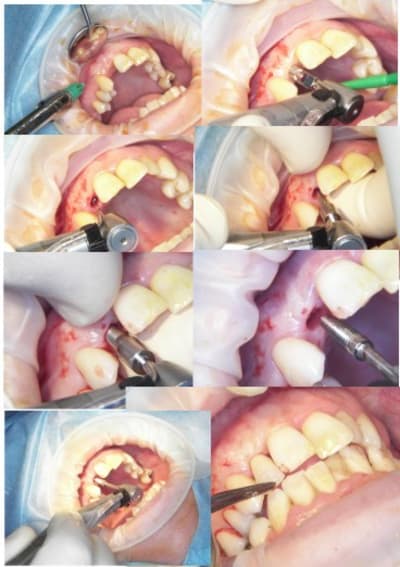

j'ai fait une bonne matinée implanto ce matin avec mélange des techniques 2 Summers avec un mélange expanseurs/condenseurs Meissinger, ostéotomes impactés pour la corticale qui faisait de la résistance, eponge pour la membrane, puis une reprise d'echec sur une mise en vitrine immédiate (fracture en mangeant une frite calcinée, à un mois!le 14/07)déposé le 15/07 mais avec mouvements pendant 24 heure et de 3.4mm j'ai du passer à 5.2!

les photos d'hier avec la mise en vitrine immediate et la reprise

--

xbk